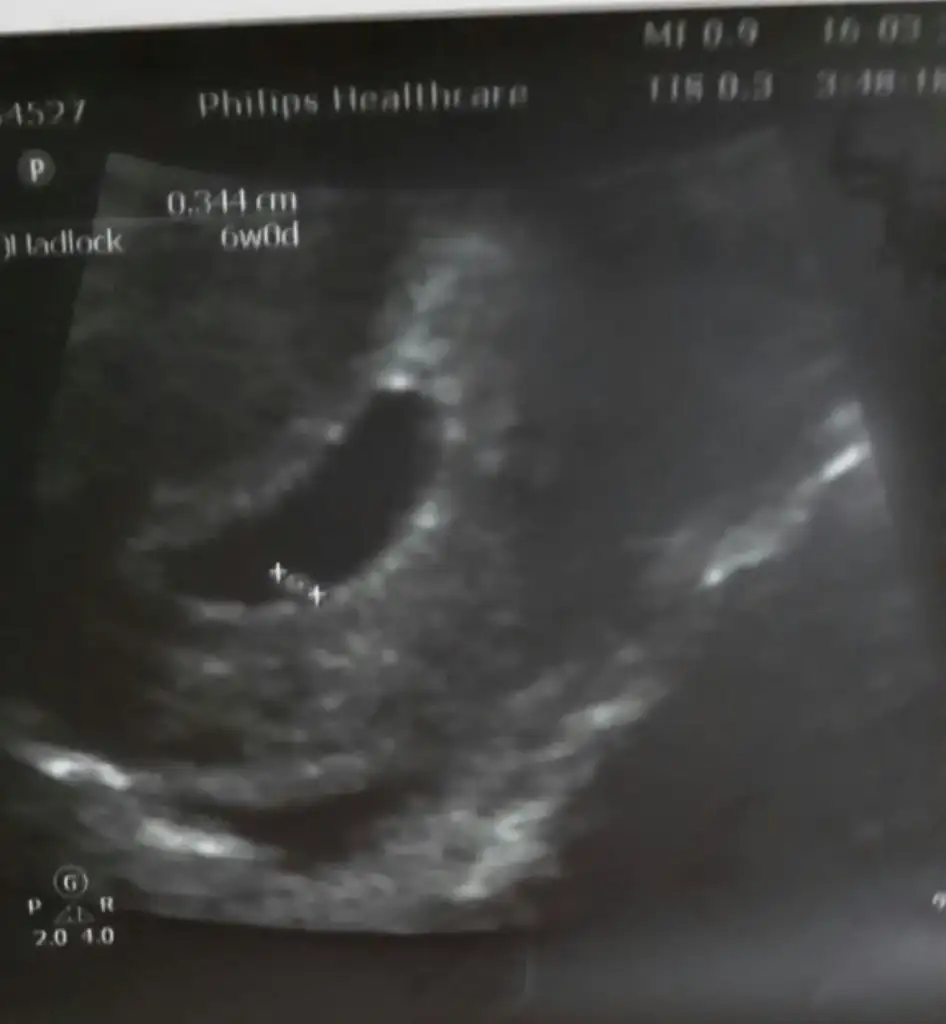

'Arkadaşlar bugün ultrasonda 6 bucuk haftalık oldugunu söyledi doktorum.Tahminde bulunabilirmisiniz..

6 haftalık ultrason görüntüsü tahminde bulunabilir misiniz